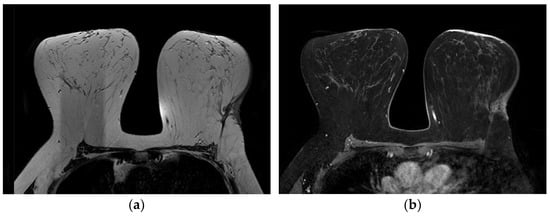

4.3. Magnetic Resonance Imaging